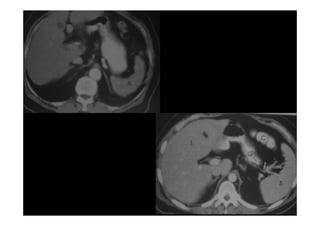

A V.PORTA(VP) FORNECE 70% DO SANGUE QUE CHEGA NO FÍGADO E

SE ORIGINA POSTERIOR AO COLO DO PÂNCREAS DA

CONFLUÊNCIA DAS VEIAS MESENTÉRICA SUPERIOR E ESPLÊNICA.

NO HILO HEPÁTICO A VP DIVIDE

NO HILO HEPÁTICO A VP DIVIDE-

-SE EM VPD E VPE.

SE EM VPD E VPE.

A A.HEPÁTICA FORNECE 30% DO SANGUE PARA O FÍGADO E 50%

DO OXIGENIO DISPONÍVEL.

GERALMENTE ORIGINA

GERALMENTE ORIGINA-

-SE DE UM RAMO DO TRONCO

SE DE UM RAMO DO TRONCO

CELÍACO(AGE+AH+AE)

NO HILO HEPÁTICO DIVIDE

NO HILO HEPÁTICO DIVIDE-

-SE EM RAMO DIREITO E ESQUERDO.

SE EM RAMO DIREITO E ESQUERDO.

AS VV. HEPÁTICAS DRENAM PARA A VCI.AS TRÊS VEIAS HEPÁTICAS

(DIREITA, MÉDIA E ESQUERDA) SITUAM

(DIREITA, MÉDIA E ESQUERDA) SITUAM-

-SE PÓSTERO

SE PÓSTERO-

-SUPERIOR

SUPERIOR

AO FÍGADO E DRENAM PARA VCI LOGO ABAIXO DO DIAFRAGMA.